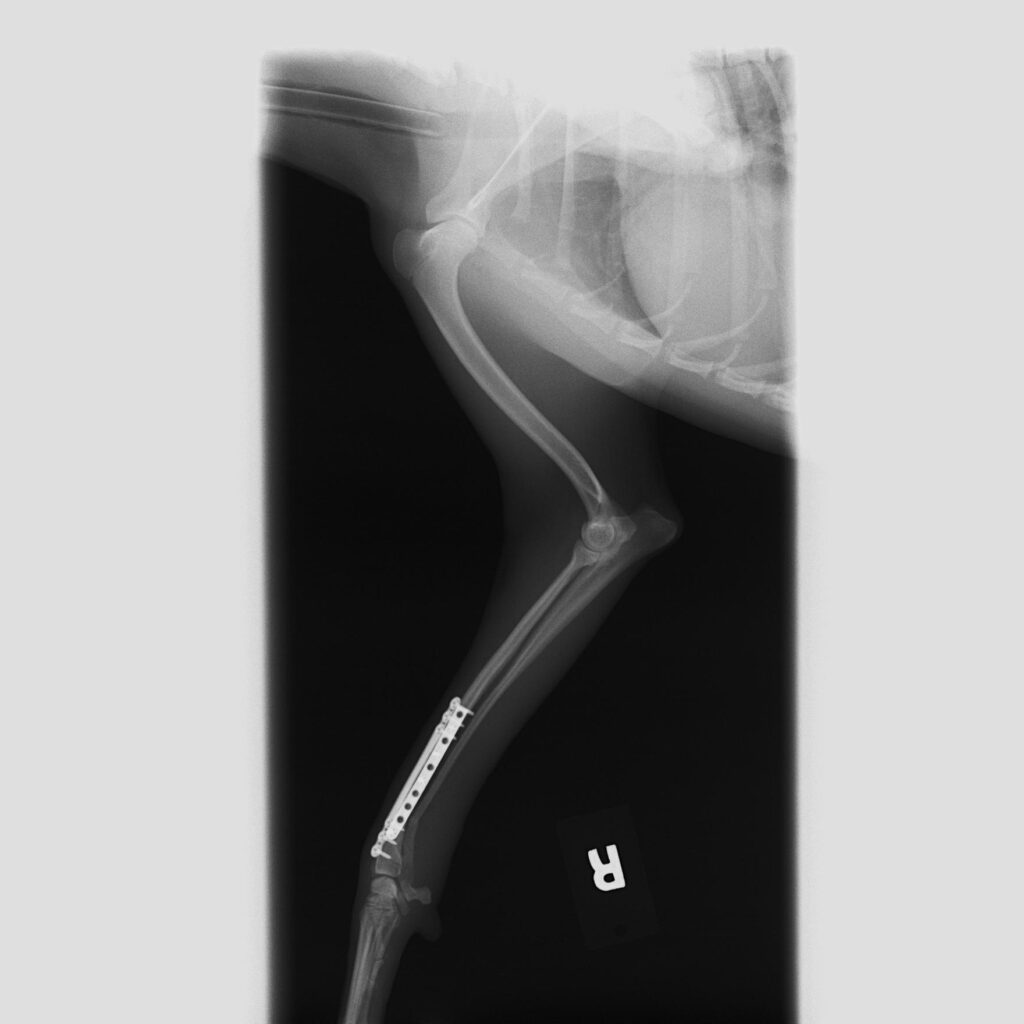

犬_整形外科_20260310 162831_診察後

処置後

全身麻酔下にて骨折の整復手術を行いました。

プレート(内固定材)を用いて骨を安定させる「プレーティング」により、骨折部の固定を行いました。

今回は元気いっぱいな性格のワンちゃんであったため、術後の安全性も考慮し、プレートを2本使用してしっかりと固定を行いました。

その後、骨の癒合を確認した段階でプレートを1本に減らし、経過を見ていく方針としました。

若齢で活動量の多い犬では、再度の負荷がかかるリスクもあるため、固定方法や術後管理が重要になります。